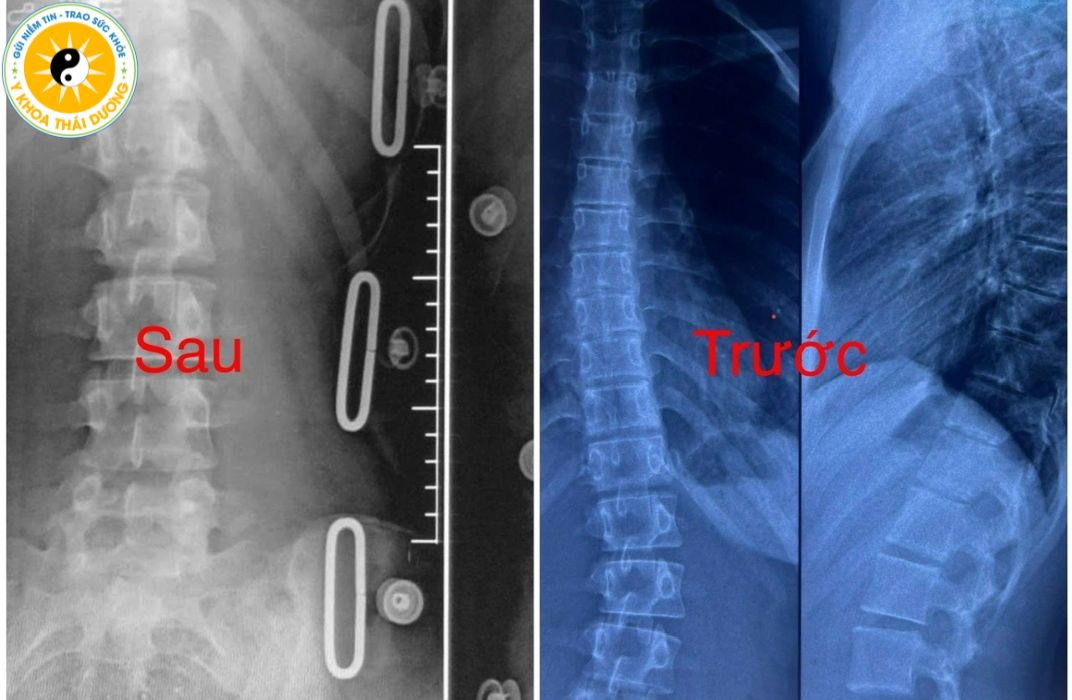

4.5. Phẫu thuật chỉnh hình (chỉ cho trường hợp đặc biệt)

Được chỉ định cho:

Góc vẹo trên 45–50 độ.

Trẻ đau nặng, biến dạng lồng ngực, ảnh hưởng tim phổi.

Phẫu thuật sẽ cố định cột sống bằng thanh kim loại nhằm ngăn vẹo tiến triển.